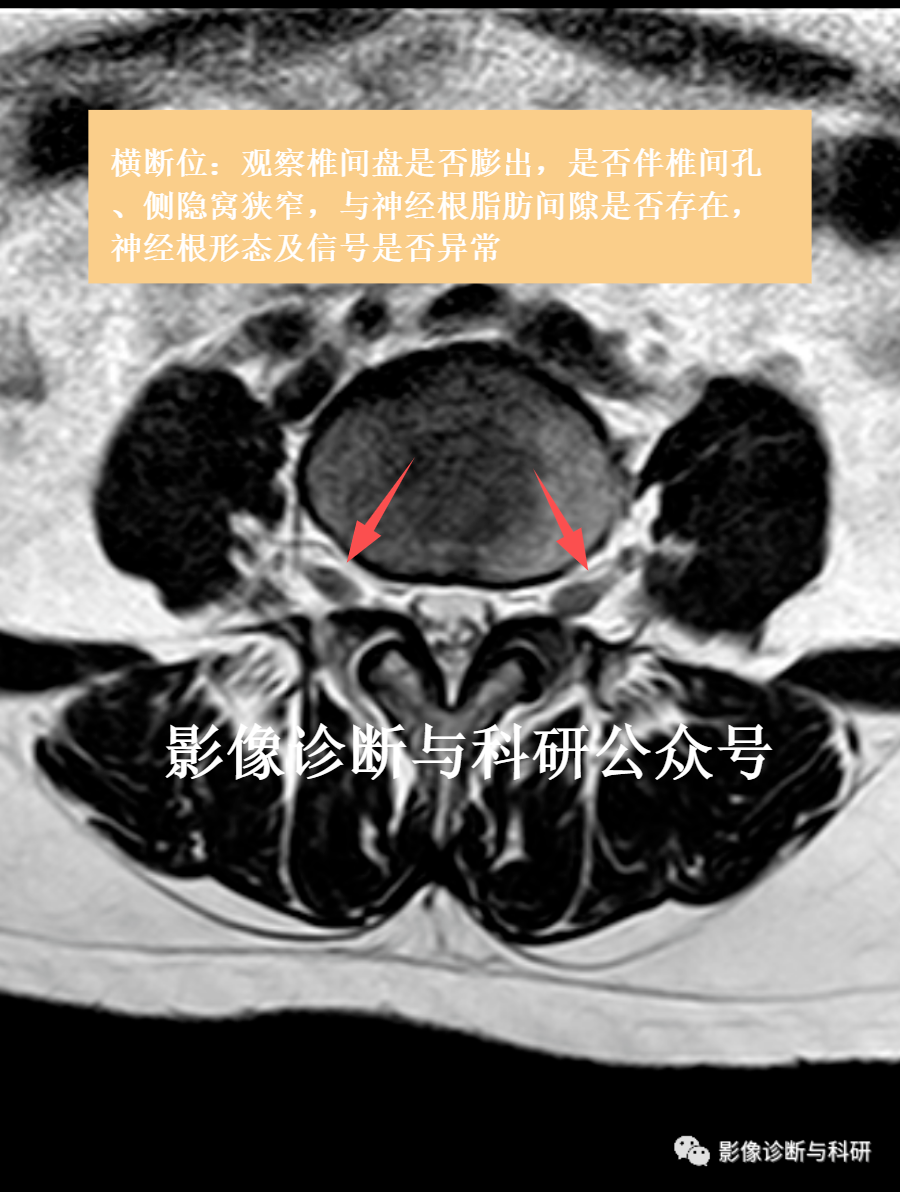

5.神经根受压

椎间盘向侧后方突出时,可造成神经根的受压,在横断面上显示较好,可观察到侧隐窝饱满,神经根淹没,或突出髓核突入椎间孔,推移椎间孔内脂肪,压迫神经根。